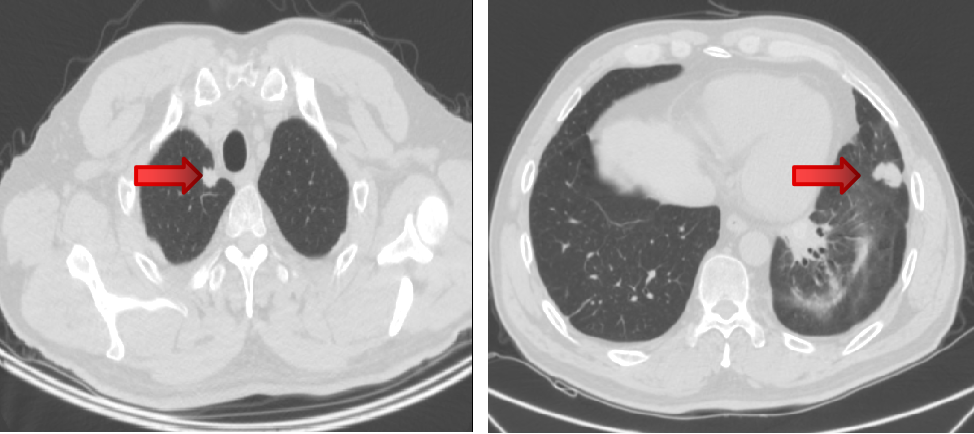

2018-1-22 PET/CT:直肠上段肠壁增厚、管腔狭窄,右侧髂内血管走行区、直肠周围间隙多个淋巴结,考虑直肠癌并淋巴结转移瘤,双肺多个小结节,未见明显代谢增高,不除外转移瘤。

2018-1-22 PET/CT

2018-10-11 胸部CT:双肺转移瘤较前进展。